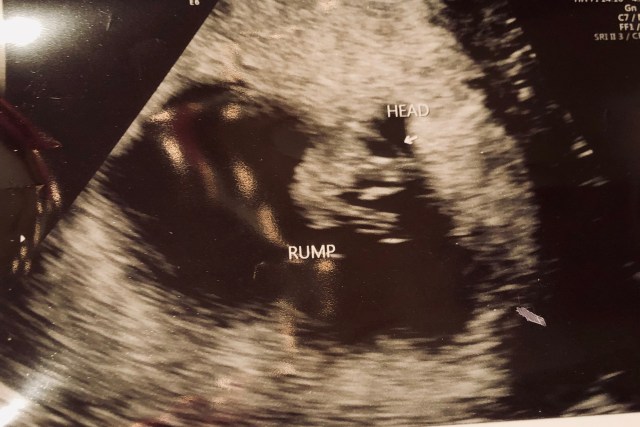

I am nine weeks pregnant. I recently had the privilege of watching that nine week person through ultrasound; I watched a tiny heart beat in quick time, in the grainy image I saw new life tucked cozily and safely within me. It’s miraculous, there hidden and quiet, life is within my body, developing rapidly. I am […]